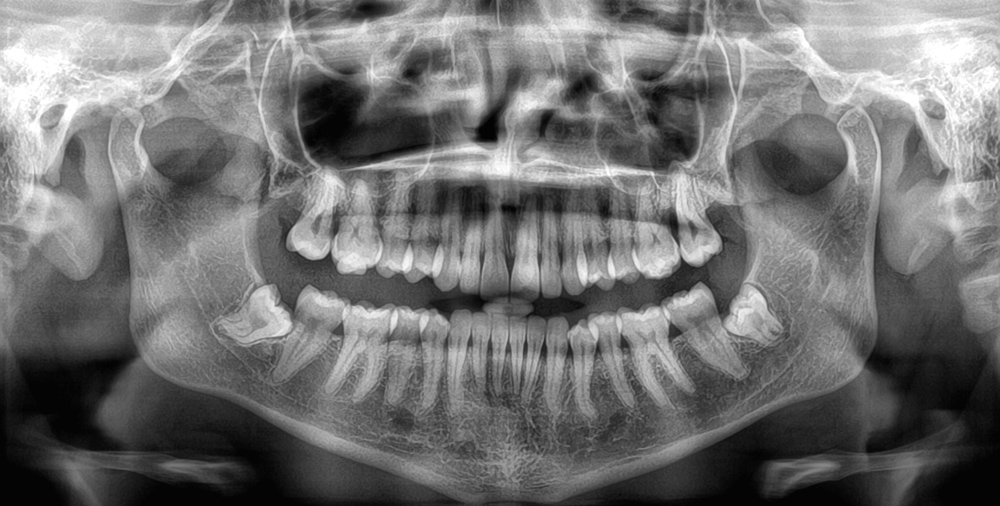

Panorâmica Topo;